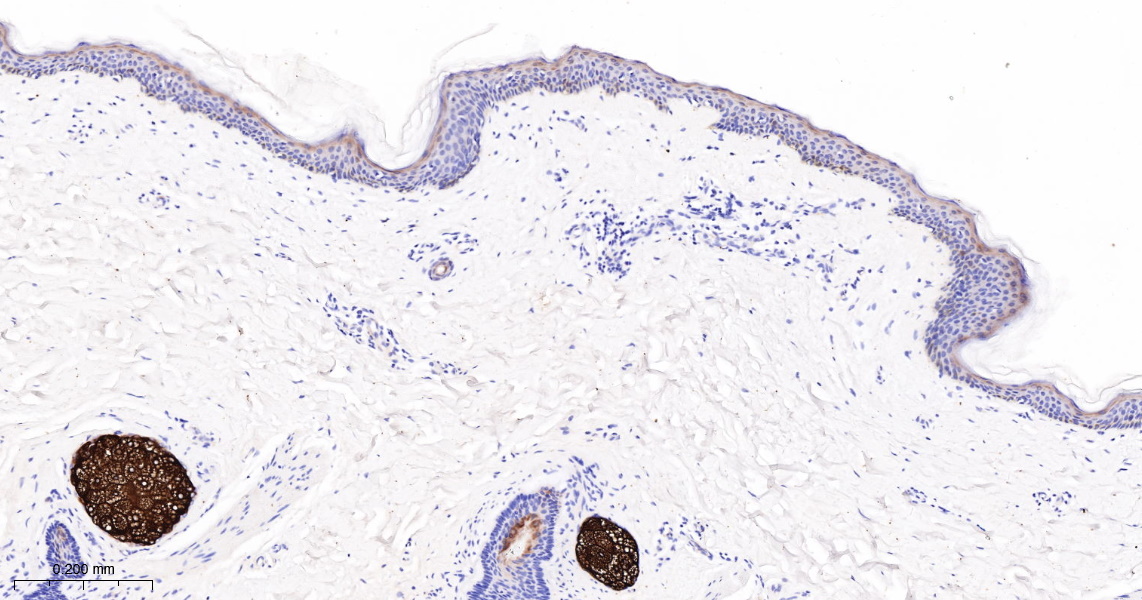

• IHC-P

IHC-P IHC-P1:100-500